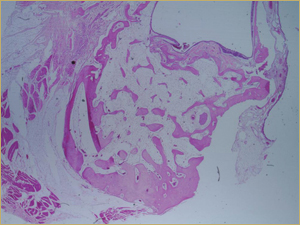

After 8 Weeks

By 8 weeks, all of the sinuses appeared histologically similar (Figs. 7–10). The mature lamellar bone that had been grafted in the autogenous bone group had been remodelled and was no longer present. Similarly, the numerous small-diameter woven bony trabeculae seen at 2 weeks in the BMP groups were no longer present. The sinuses all contained mature, small-diameter lamellar bony trabeculae. No qualitative histologic differences were apparent among the 5 treatment groups at 8 weeks (Figs. 7–10).

Figure 10: Low-power histologic examination of rabbit maxillary sinus augmented with bone morphogenetic protein in demineralized bone matrix at 8 weeks after procedure. H&E stain, 100× magnification.